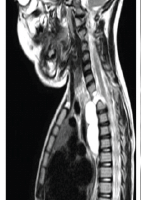

Radiology

X-rays and computed tomography (CT) scan confirmed a neglected posterior dislocation of the right hip with a comminuted fracture of the acetabulum involving the posterior wall and column (Fig. 1-7). The femoral head showed early degenerative changes.